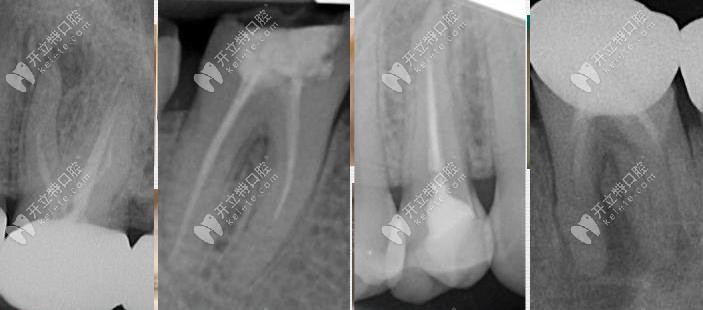

根管治療修復(fù)

根管治療修復(fù)頻道為您提供根管治療修復(fù),根管治療冠修復(fù),根管治療后牙冠修復(fù),根管治療修復(fù)價(jià)格等信息。查找更多關(guān)于根管治療修復(fù)的信息,就訪問(wèn)開(kāi)立特口腔網(wǎng)。

根管治療修復(fù)顯微根管治療發(fā)布時(shí)間: 2025-04-25

你是否也有寧愿拔牙也不做根管治療的想法呢?如果有的話(huà),也是對(duì)的,畢竟根管治療上雖然可以保留部分牙根,對(duì)于醫(yī)生的操作要求也比較高。所以做根管治療后必要注意這幾大不成功表現(xiàn)。